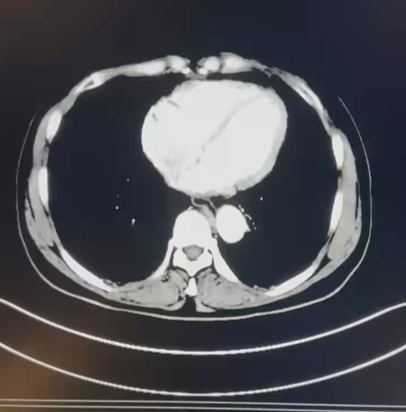

CT:1. 左肾下极占位性病变:肾 CA? 2. 双肺多发囊肿;3. 双肾小结石;4. 肝 S4 段强化灶;5. 肝多发囊肿。

2021.10.14 行腹腔镜下左肾部分切除术。

术后病理:乳头状肾细胞癌,II 型,ISUP 分级 G3 级。脉管内未见瘤栓,未见神经周侵犯。